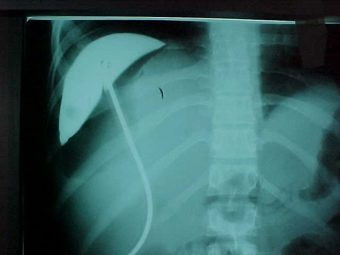

Abcseso Subfrénico

Envíado por Dr. Carlos Edgardo Escobar